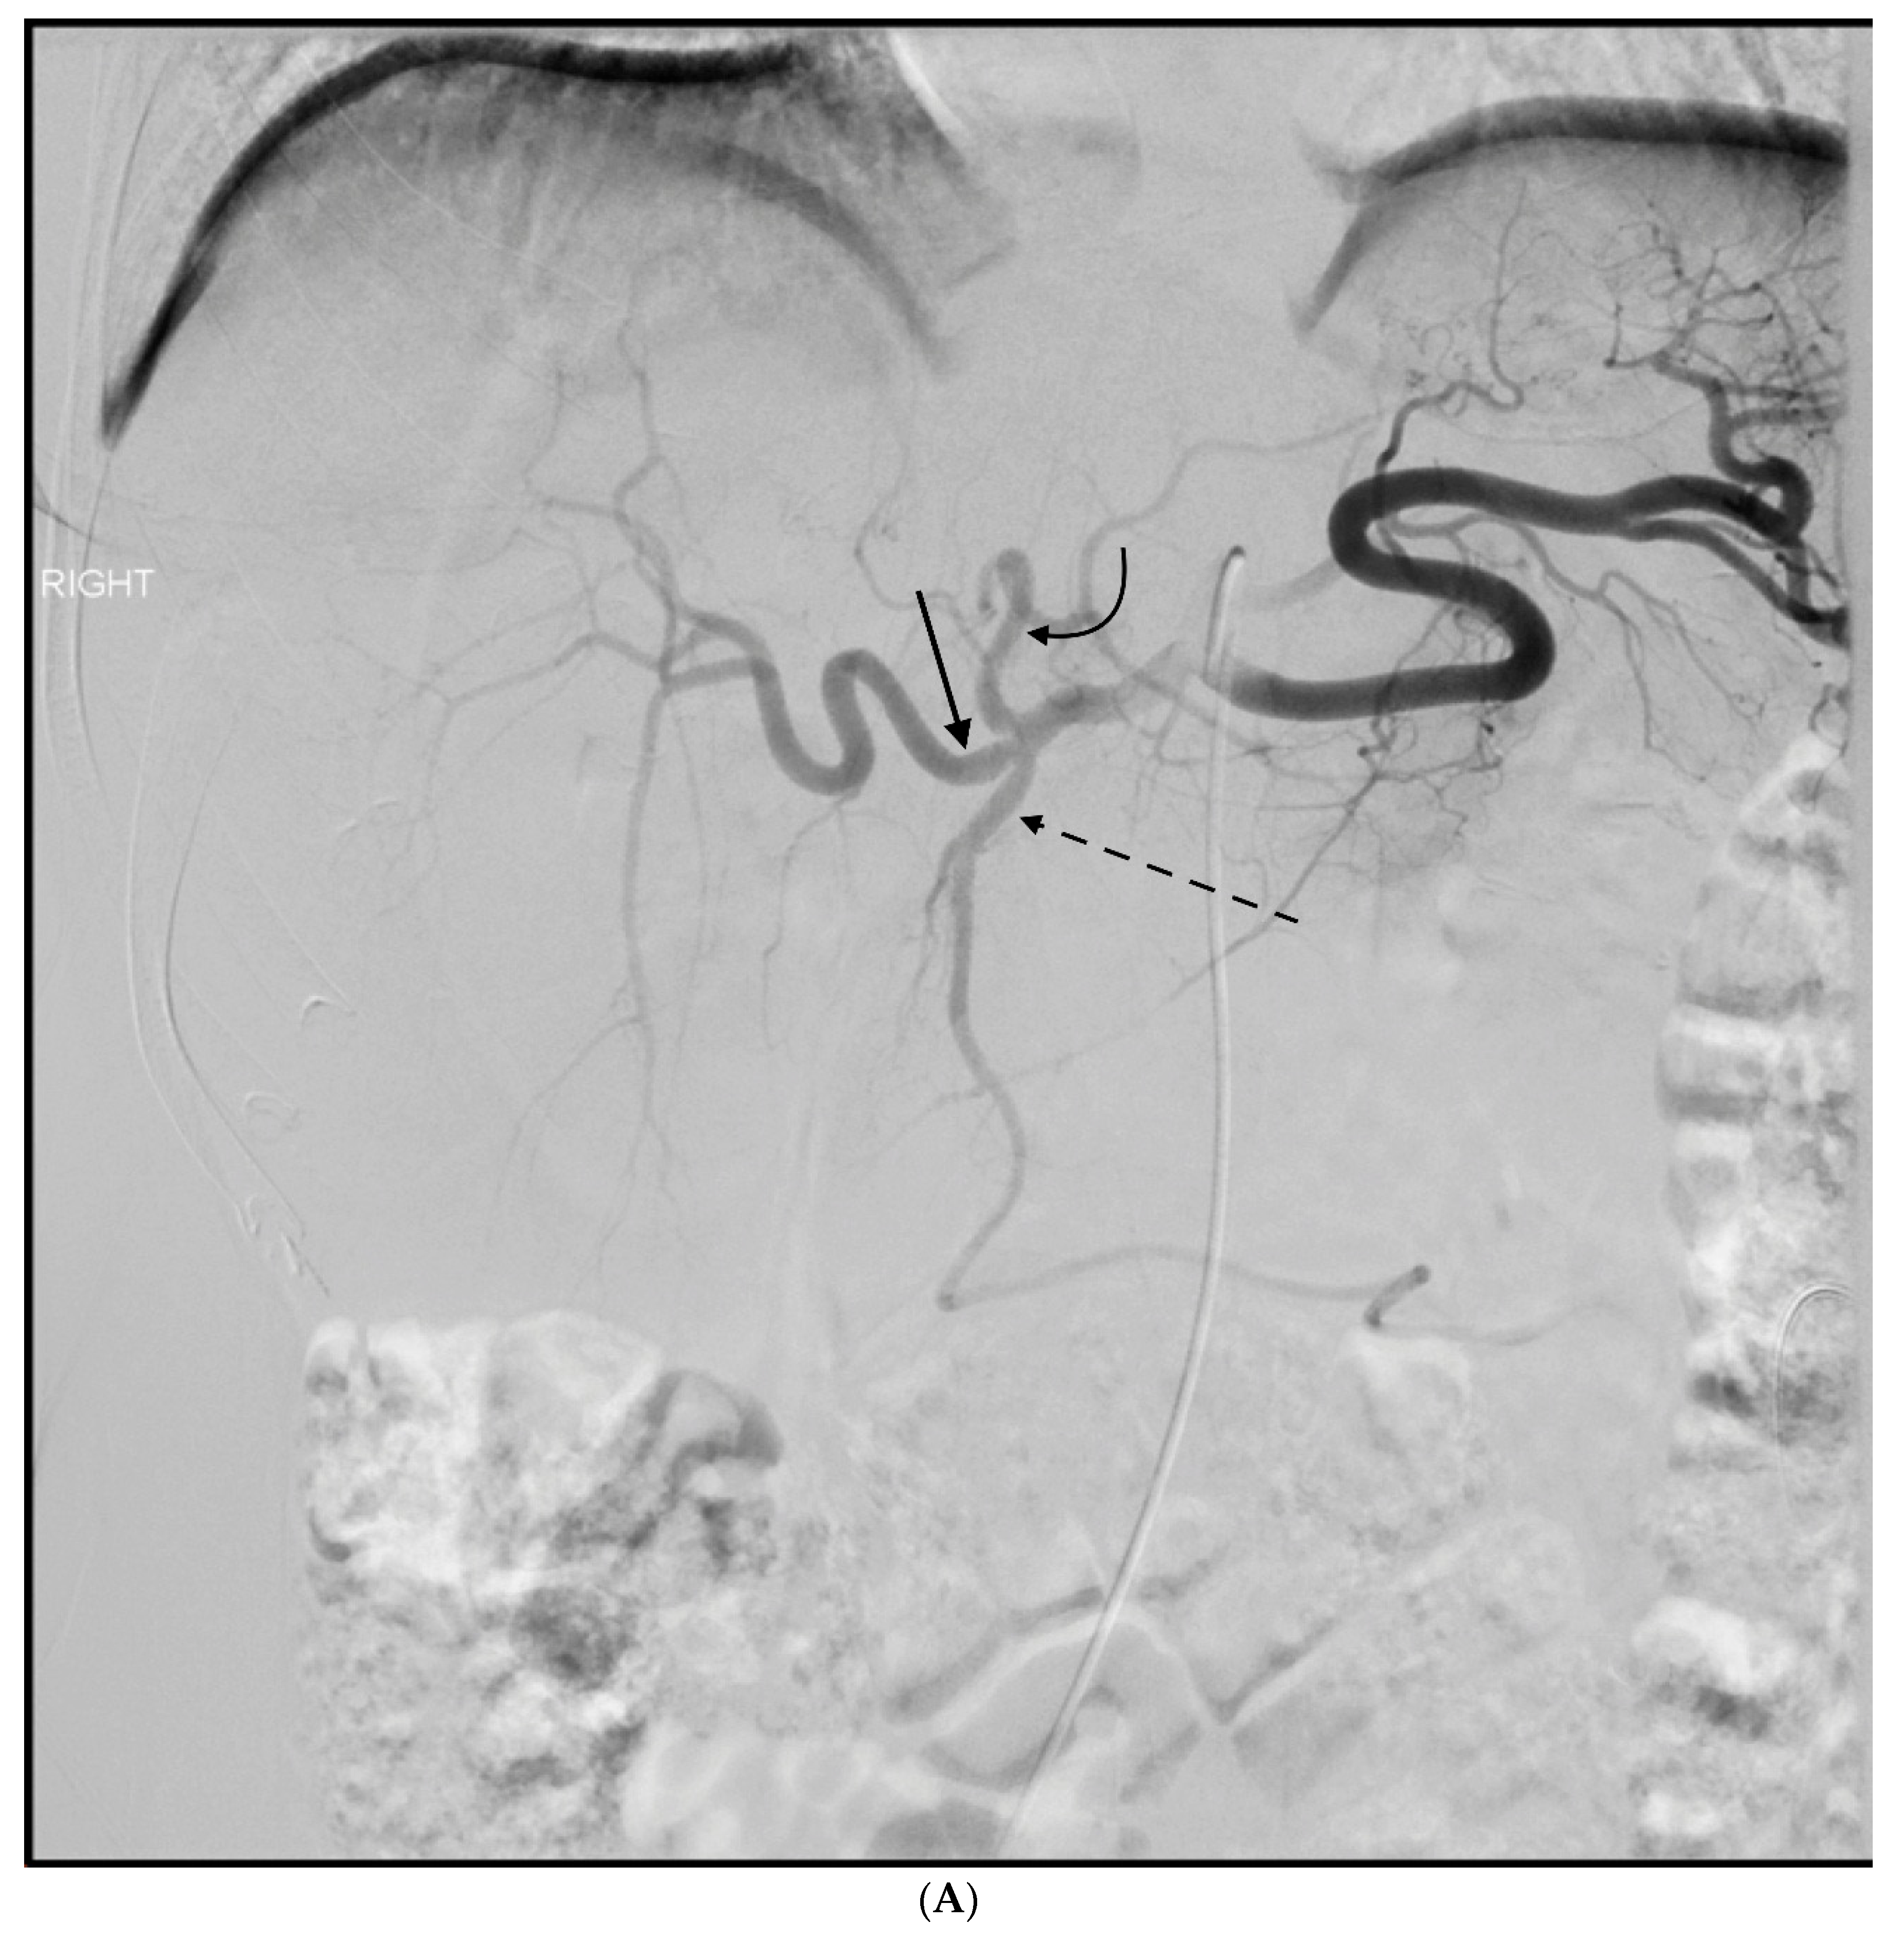

2. Anatomy and Embryology of Gastroduodenal Artery

3. GDA Embolization in Gastrointestinal Bleeding

4. GDA Pseudoaneurysm Embolization

5. Pre-Y-90 GDA Embolization